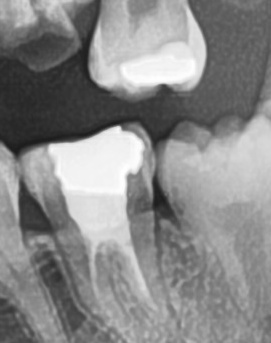

어금니 뒤 잇몸 부음의 문제는 사랑니가 원인이 되는 경우도 많은데 사랑니는 특히 현대인들의 경우 제대로 나오지 못하고 매복되는 경우가 많으며 완전히 나오지 않은 사랑니는 잇몸 속에서 자라면서 주변 잇몸을 자극할 수 있고, 일부만 노출되면 음식물이 끼면서 염증이 생기기도 하며 특히 어금니 뒤쪽 잇몸이 붓고 지속적으로 불편함을 느낀다면 사랑니로 인한 염증을 의심해 볼 수 있어요. 사랑니로 인한 문제의 경우 단순한 소염제나 구강 세정제로 해결되지 않고, 사랑니를 발치해야 잇몸 염증이 해결되는 경우가 많이 있어요

결론적으로는 통증이 심하거나 염증이 오래 지속되는 경우에는 치과를 방문해서 정확한 진단을 받는 것이 중요한데 단순한 잇몸 염증이라면 치석 제거와 항생제 치료로 호전될 수 있지만, 치주염이 진행된 경우라면 보다 적극적인 치료가 필요할 수 있어요. 만약 사랑니로 인해 잇몸이 자꾸 붓는다면 사랑니 발치를 고려해야 하겠고 사랑니가 완전히 매복되어 있다면 수술적인 방법으로 제거해야 할 수도 있어요. 특히 반복적으로 붓는다면 사랑니 검사를 받아보거나, 치과에서 정밀 검진을 통해 치주 상태를 확인하는 것이 필요하다는 점에서 어금니 근처의 잇몸이 반복적으로 불편하다면 꼭 치과를 찾아보시길 바라고 있어요